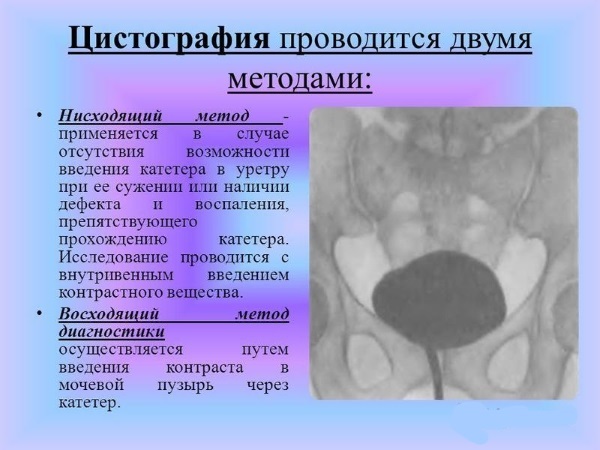

Медицинские изображения и примеры эксреторной цистографии